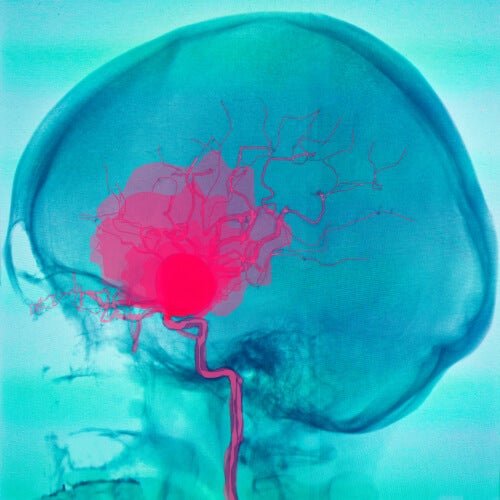

La paralisi cerebrale è una disabilità causata da una lesione cerebrale. La lesione limita l’attività del soggetto, in quanto ne influenza sia la mobilità che la postura. Gli scienziati definiscono la paralisi come un gruppo di disturbi permanenti del movimento.

In genere si verifica durante lo sviluppo del feto o nei primi anni di vita. Inoltre, può essere accompagnata da alterazioni della sensibilità e disturbi cognitivi. Per tale ragione, viene considerata una disabilità multipla.

Come abbiamo accennato, la paralisi cerebrale in realtà si riferisce a una serie di disturbi che influenzano il movimento, l’equilibrio e la postura. Di solito compare nei primi anni di vita, dato che nella maggior parte dei casi si sviluppa durante la gravidanza.

Comprende in genere altri disturbi. Per esempio, risulta complicato svolgere semplici attività come camminare o scrivere. È frequente, inoltre, la coesistenza con disabilità mentali e altre patologie. Ciò, ovviamente, dipende dalla posizione e dall’entità della lesione cerebrale.

È una patologia permanente che non tende a cambiare nel tempo. Questo perché la lesione cerebrale è irreversibile e, con essa, il danno neurologico. Verificandosi di norma prima dei 3 anni, i sintomi sono evidenti sin da subito.